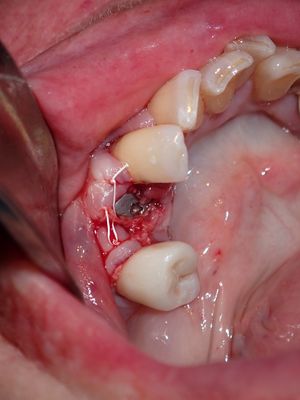

Atraumatic exo, about 2mm buccal bone loss, might have been present post exo but very thin, implant ostoetomy underprepared, dense bone at apex of socket, implant placed with good stabitliy, buccal flapped, socket and buccal grafted with allograft (small amount of xeno) folloewd by collagen membrane, healing abutment placed

PB170016.JPG